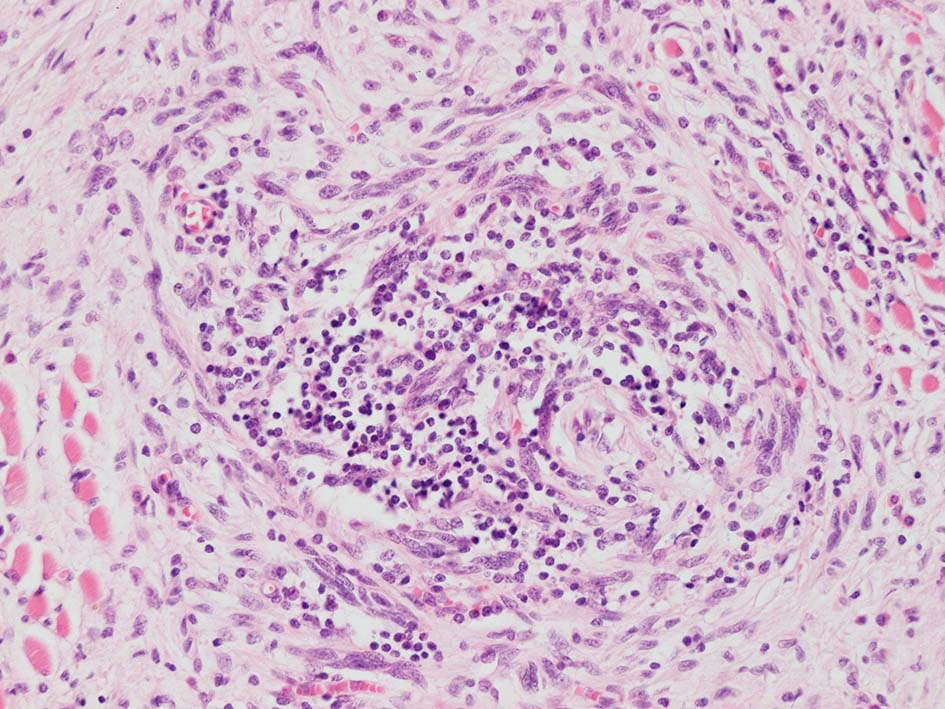

リンパ濾胞が細血管周囲に形成され, この部分に異型といえる細胞が増加している(S100+)

再発腫瘤病変の組織像